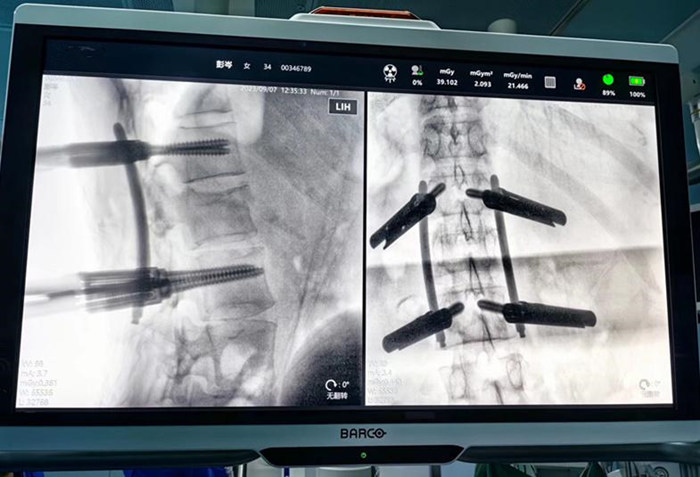

术中朱院长在机器手臂辅助下行精准、微创置钉

术中朱院长在机器手臂辅助下行精准微创置钉

手术医师在机器人三维影像智能引导下,操作机械臂通过微创的方式,在脊柱上“打钉子”,使手术切口更小、损伤更小、出血更少、术后康复更快。术后影像显示,钉钉子的大小、位置、角度都接近完美。

术中透视见骨折复位完美,螺钉位置满意